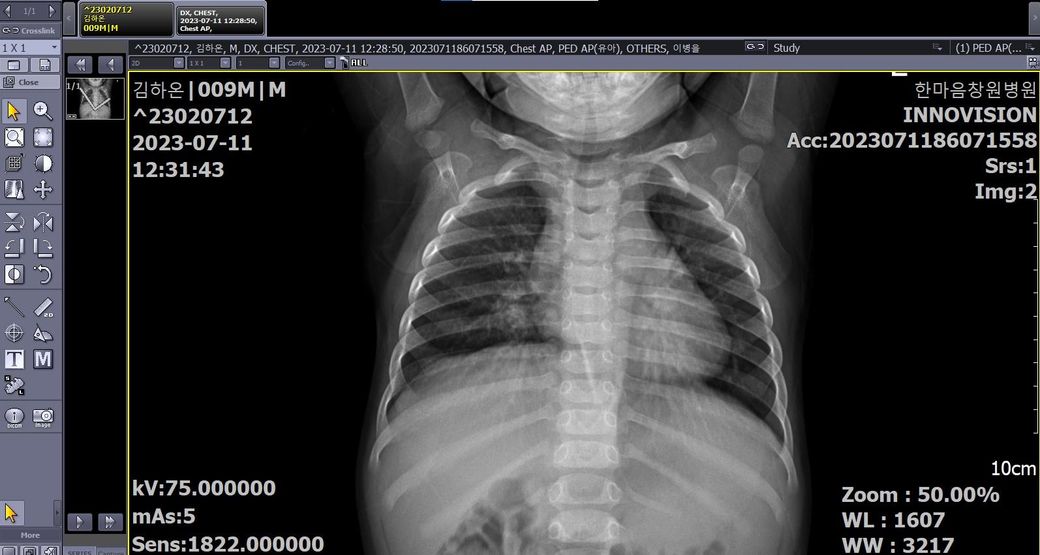

X-ray 별도 첨부 드립니다.

• 1번 째 사진

• 2번 째 사진